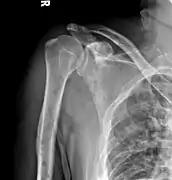

The diagnostic examination of a person with suspected multiple myeloma typically includes a skeletal survey. This is a series of X-rays of the skull, axial skeleton, and proximal long bones. Myeloma activity sometimes appears as "lytic lesions" (with local disappearance of normal bone due to resorption) or as "punched-out lesions" on the skull X-ray ("raindrop skull"). Lesions may also be sclerotic, which is seen as radiodense.[70] Overall, the radiodensity of myeloma is between −30 and 120 Hounsfield units (HU).[71] Magnetic resonance imaging is more sensitive than simple X-rays in the detection of lytic lesions, and may supersede a skeletal survey, especially when vertebral disease is suspected. Occasionally, a CT scan is performed to measure the size of soft-tissue plasmacytomas. Nuclear Medicine Bone scans are typically not of any additional value in the workup of people with myeloma (no new bone formation; lytic lesions not well visualized on nuclear bone scan).

- Multiple myeloma in the upper arm